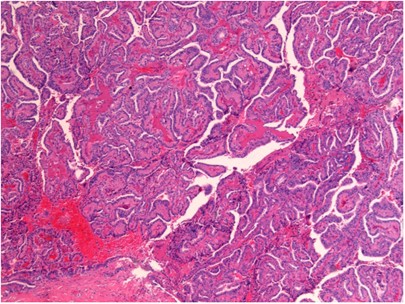

Papillary Carcinoma